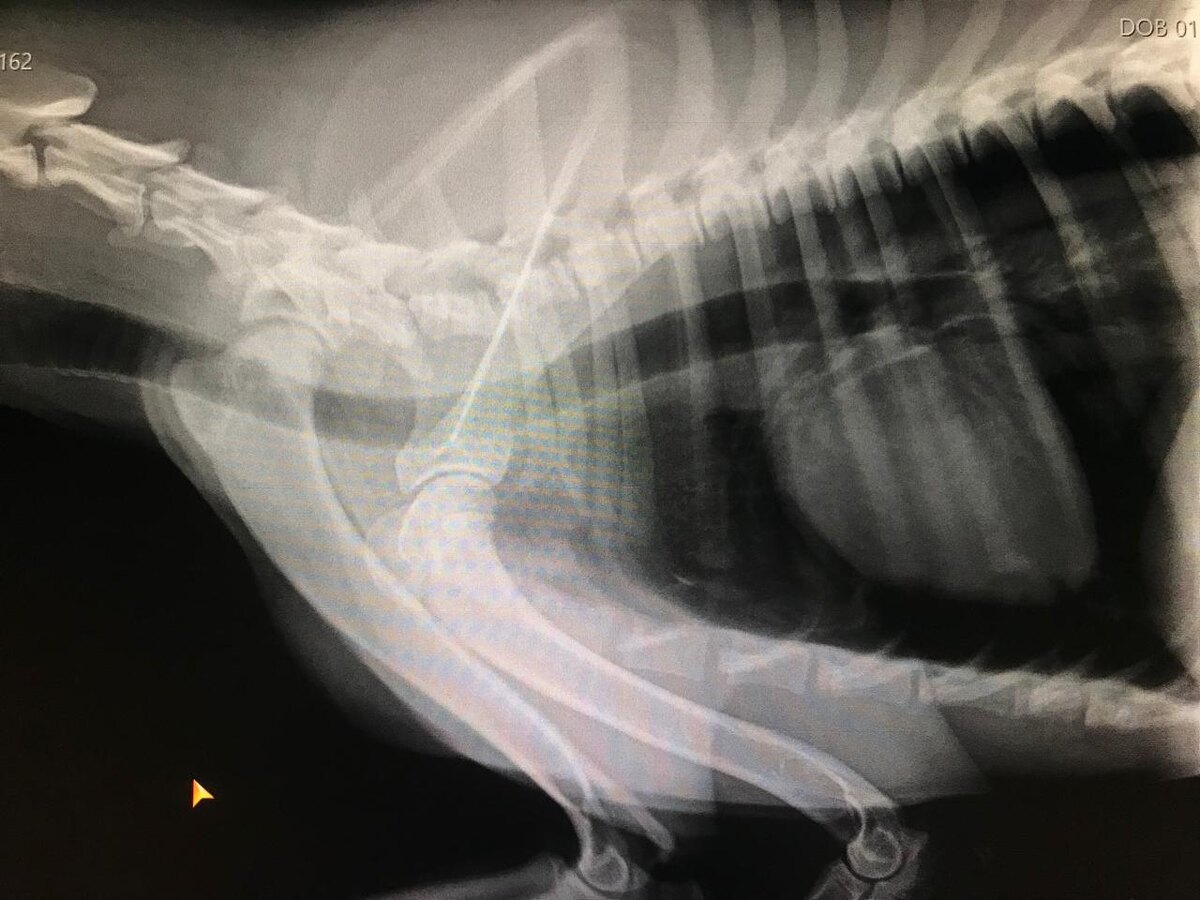

Пёсик (мальчик) в тяжелом состоянии.

У него ЧМТ, ушиб лёгких, пневмоторакс и перелом бедра.

Мальчику примерно 9 месяцев. Назвали Юрик.

Завтра требуется срочная операция. Сегодня за прием оплатили.

Сумма к сбору на операцию и стационар 20 000 рублей.